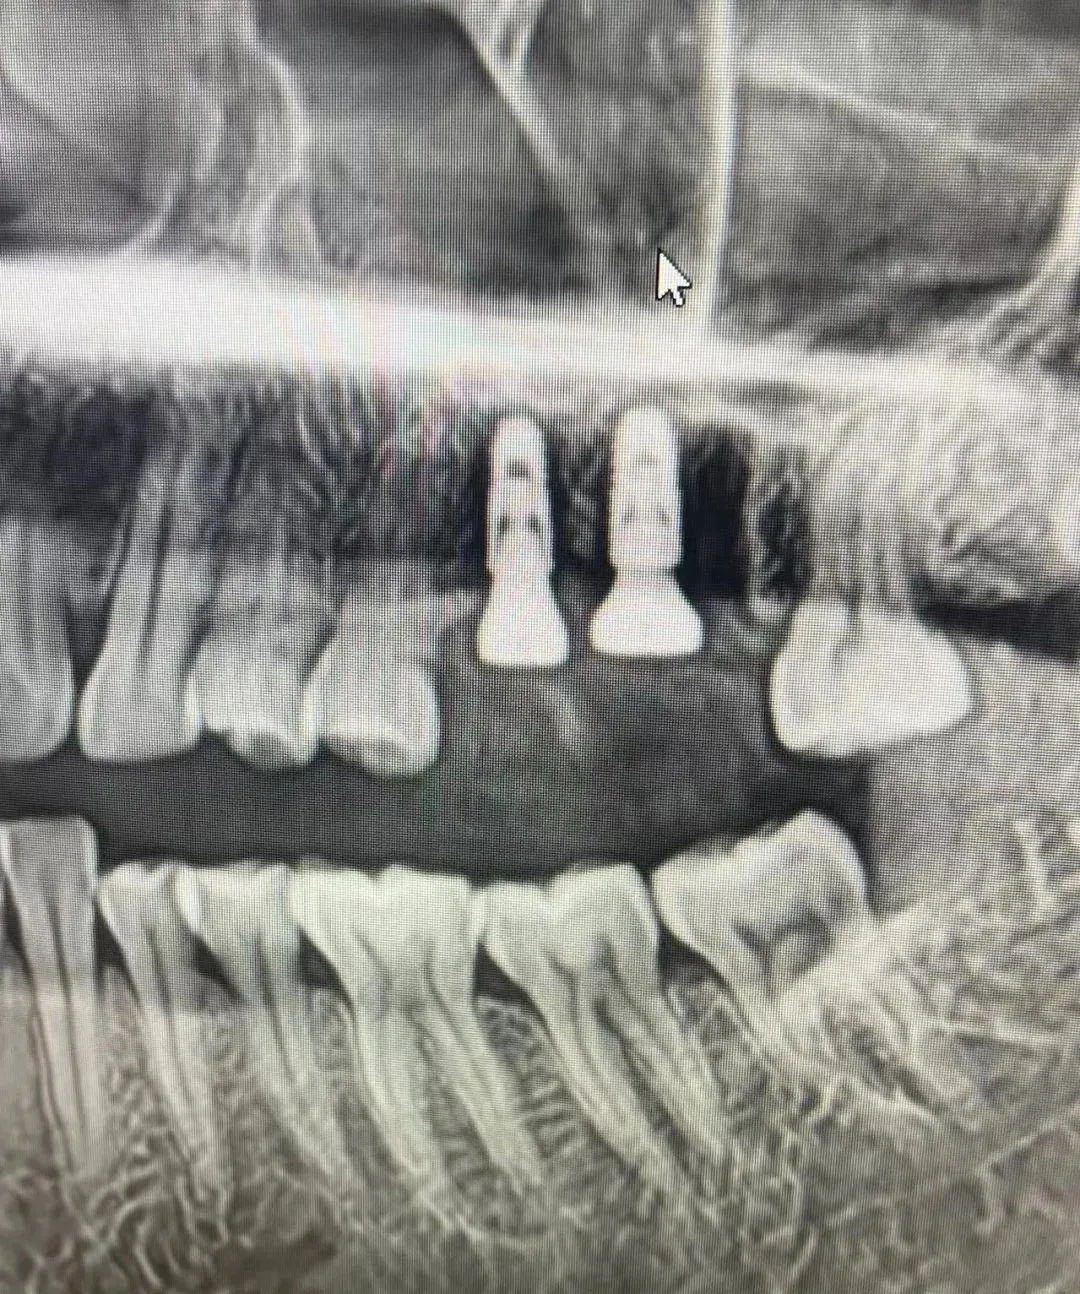

7、种植影像学分析;可以获得骨高度 ,骨宽度信息 ,甚至可以模拟种植体植入位点

六、学员回家后部分病例